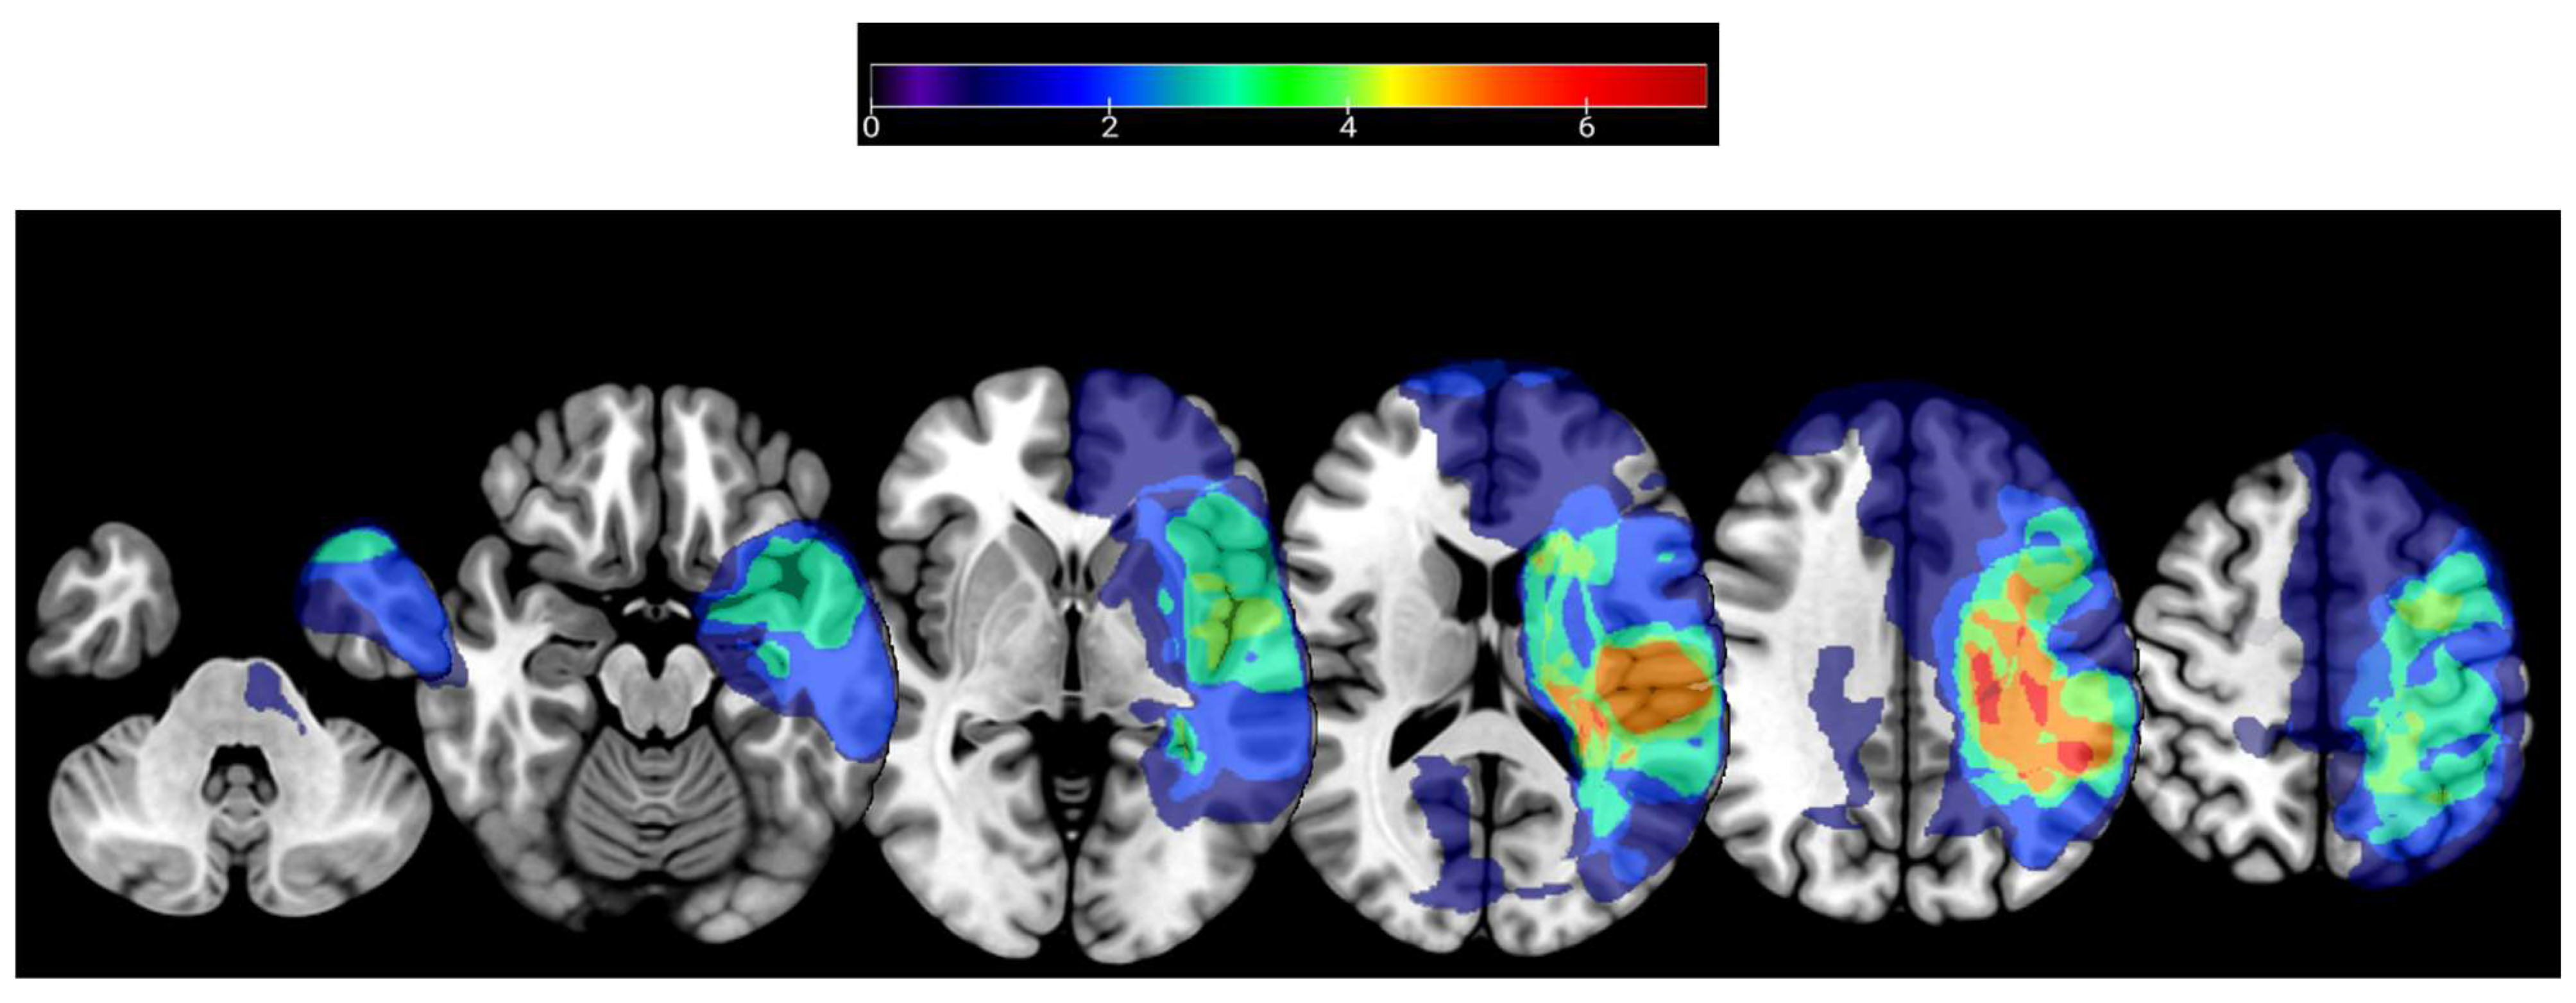

2.2.3. MRI Acquisition

3.1. Participant Characteristics